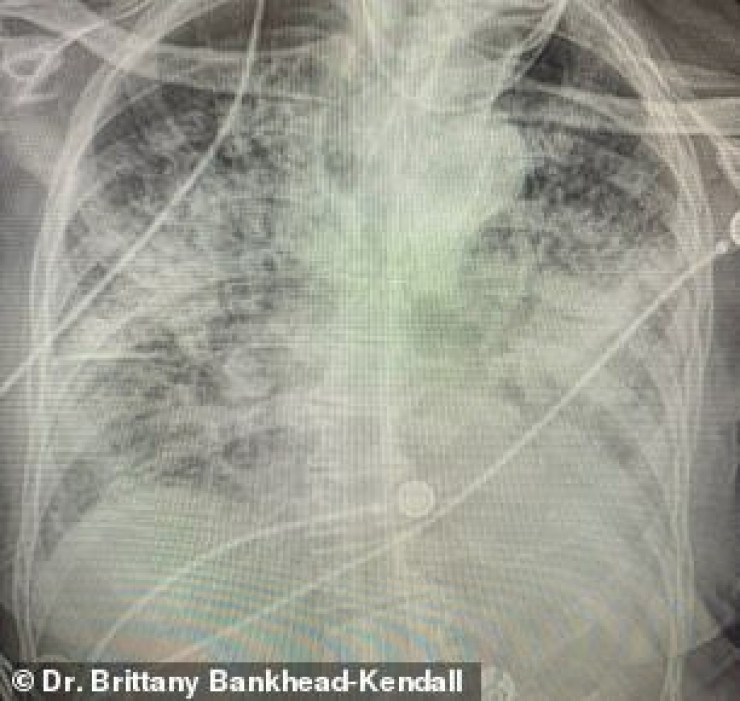

Доцент Центра медицинских наук Техасского технологического университета, доктор Бриттани Бэнкхед-Кендалл показала три рентгеновских снимка легких: здорового человека, курильщика и пациента с коронавирусом.

По словам хирурга, легкие выздоровевших пациентов с COVID-19 выглядят намного хуже, чем у курильщиков. Снимок выглядел почти полностью белым. Врач пояснила, что помутнение легких обычно указывает на то, что они наполнены такими веществами, как жидкость или бактерии, а также плотными рубцами и повреждениями.

У курильщика они частично побелели от рубцов, и снимок выглядит слегка туманным.